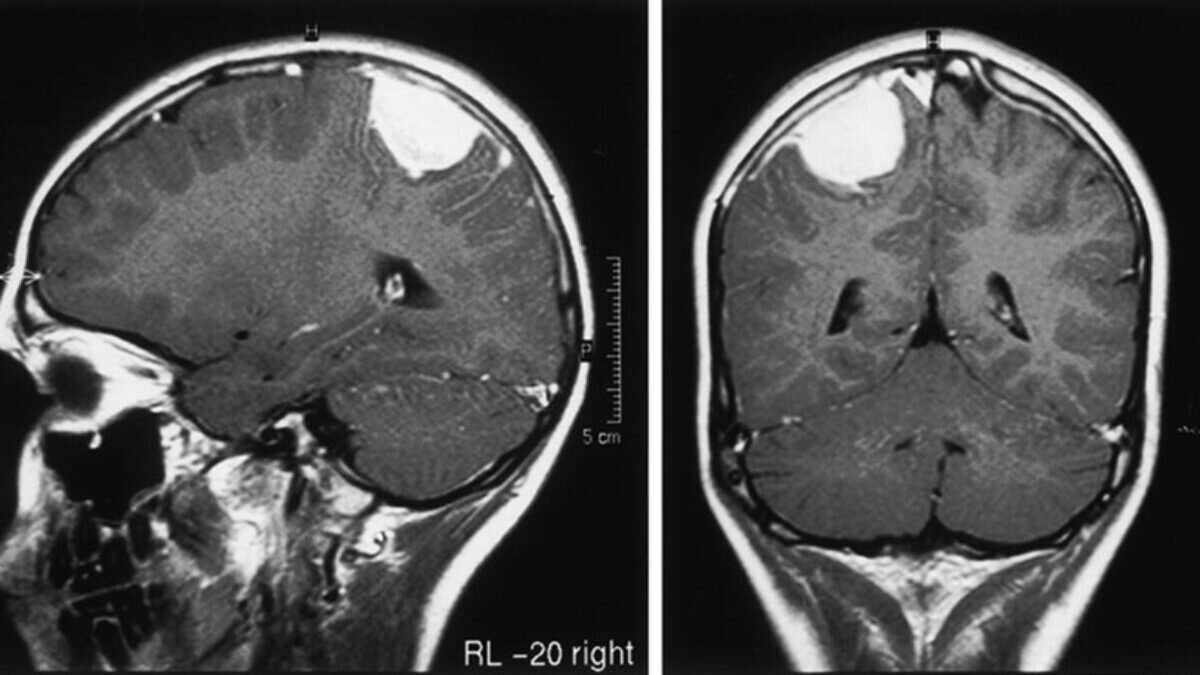

Врачи удалили кисту в головном мозге у годовалого малыша